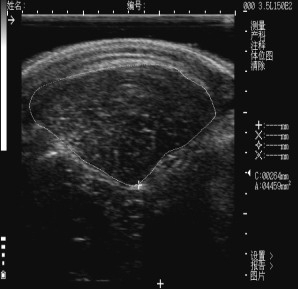

背最长肌横截面的面积也就是眼肌面积,是*猪种**场测定的一个重要指标,与瘦肉率相关。采用B超测定时,背膘厚、眼肌面积的测定部位是倒数第3~4肋间距背中线5cm处。

在实际的测定过程中,我们见到的大多数眼肌面积图像是黑白的B超图片,或者是一张插画。

倒数第3~4肋间的CT扫描图,距背中线5cm处的背膘厚和眼肌。点击右边肌肉还有对肌肉的英文说明,点图中眼肌位置,有关于眼肌的介绍。